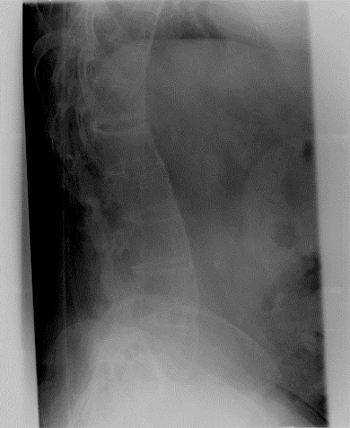

Same patient's lumbar spine x-ray, showing the classic "bamboo spine" appearance.